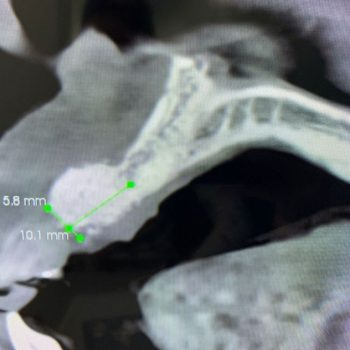

Suyak payvandlash tatqiqot jarayoni

Inmediate load implant + Integros Bone Plus XS

Integros Bone Plus XS foydalanib yangilangan suyak.

Integros Bone Plus XS’dan foydalanib tezkor o’rnatish implanti

Bone regeneration using Integros Bone Plus XS